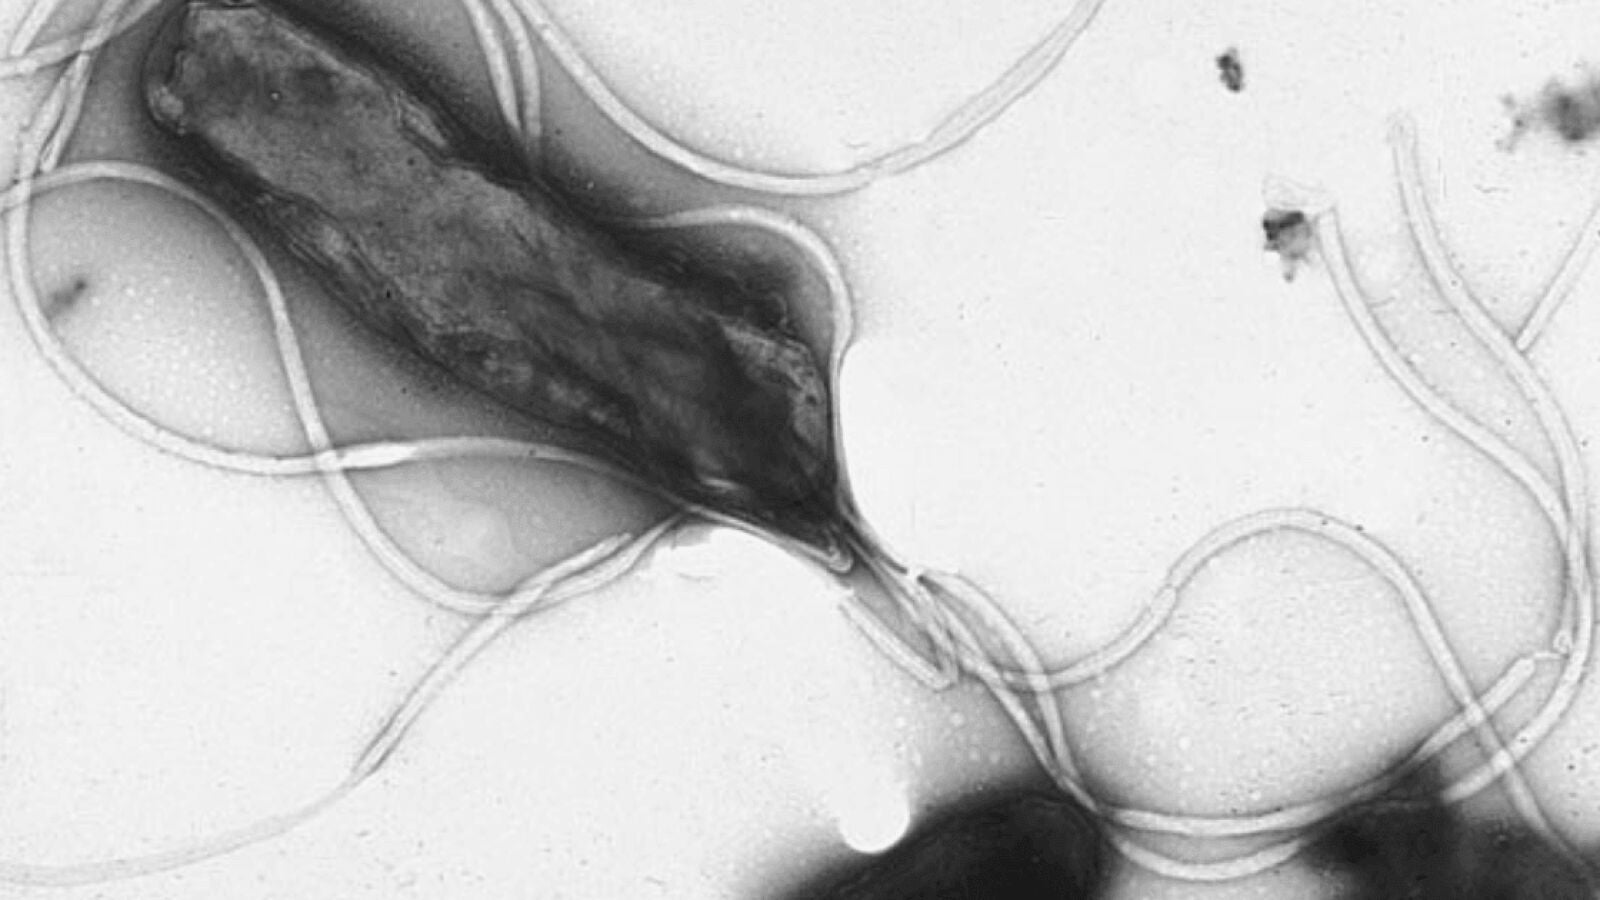

"La H. pylori afecta principalmente al revestimiento interno del estómago y puede causar un carcinoma gástrico no cardias, un tipo de cáncer que se desarrolla en las células que producen mucosa, así como un linfoma gástrico de crecimiento lento que surge en el tejido del sistema inmunológico de este órgano", explica a SINC Jin Young Park, miembro de Agencia Internacional para la Investigación del Cáncer y autora principal del artículo.

"Los seres humanos son el único reservorio significativo conocido de H. pylori. Se cree que el contacto de persona a persona es la principal vía de transmisión, aunque también hay indicios de transmisiones oral-orales, fecales-orales, acuosas e iatrogénicas (provocadas por un tratamiento médico)", explica Park.